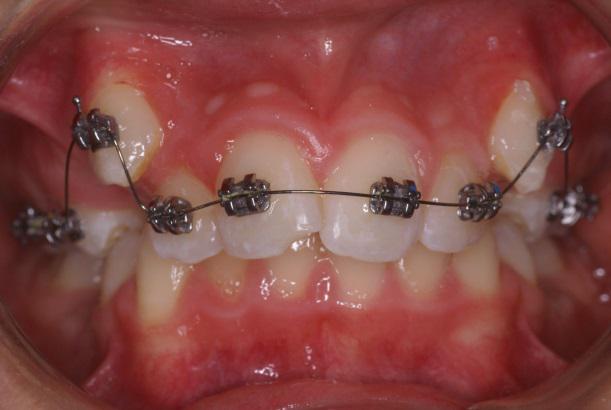

Orthodontie vestibulaire

Les progrès en matériau de collage et en métallotechnie permettent de proposer des appareillages plus modernes métalliques et en céramique pour le confort du patient et une pratique plus aisée

Toutes les bagues sont collées y compris les molaires afin de minimiser les risques de caries des bagues qui entourent les dents.

Bagues auto-ligaturantes

Les bagues sont maintenant auto-ligaturantes, il n’existe plus de ligature ( lien bloquant le fil orthodontique dans la rainure de la bague) l’avantage est pratique pour le praticien et moins de gène et une meilleure hygiène pour le patient.